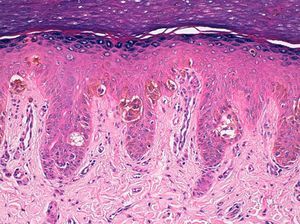

Se decidió realizar una biopsia-punch del hiponiquio que mostró una proliferación melanocítica juntural de aspecto benigno, con melanocitos dispuestos en nidos y células aisladas intraepidérmicas (fig. 3). El estudio histológico de un fragmento distal de la lámina ungueal demostró la presencia de depósitos melánicos. El diagnóstico final fue de nevus melanocítico congénito acral periungueal y subungueal. Tras 6 meses de seguimiento el componente névico periungueal se observa de un modo más evidente y el tamaño de la lesión permanece estable (fig. 1C y fig. 2C).

Hiperplasia epidérmica y proliferación de melanocitos de núcleo pequeño, sin atipia ni pleomorfismo, dispuestos en nidos de tamaño variable en la porción inferior del epitelio y también en forma de células individuales con patrón pagetoide en los niveles altos del epitelio (hematoxilina-eosina x 100).